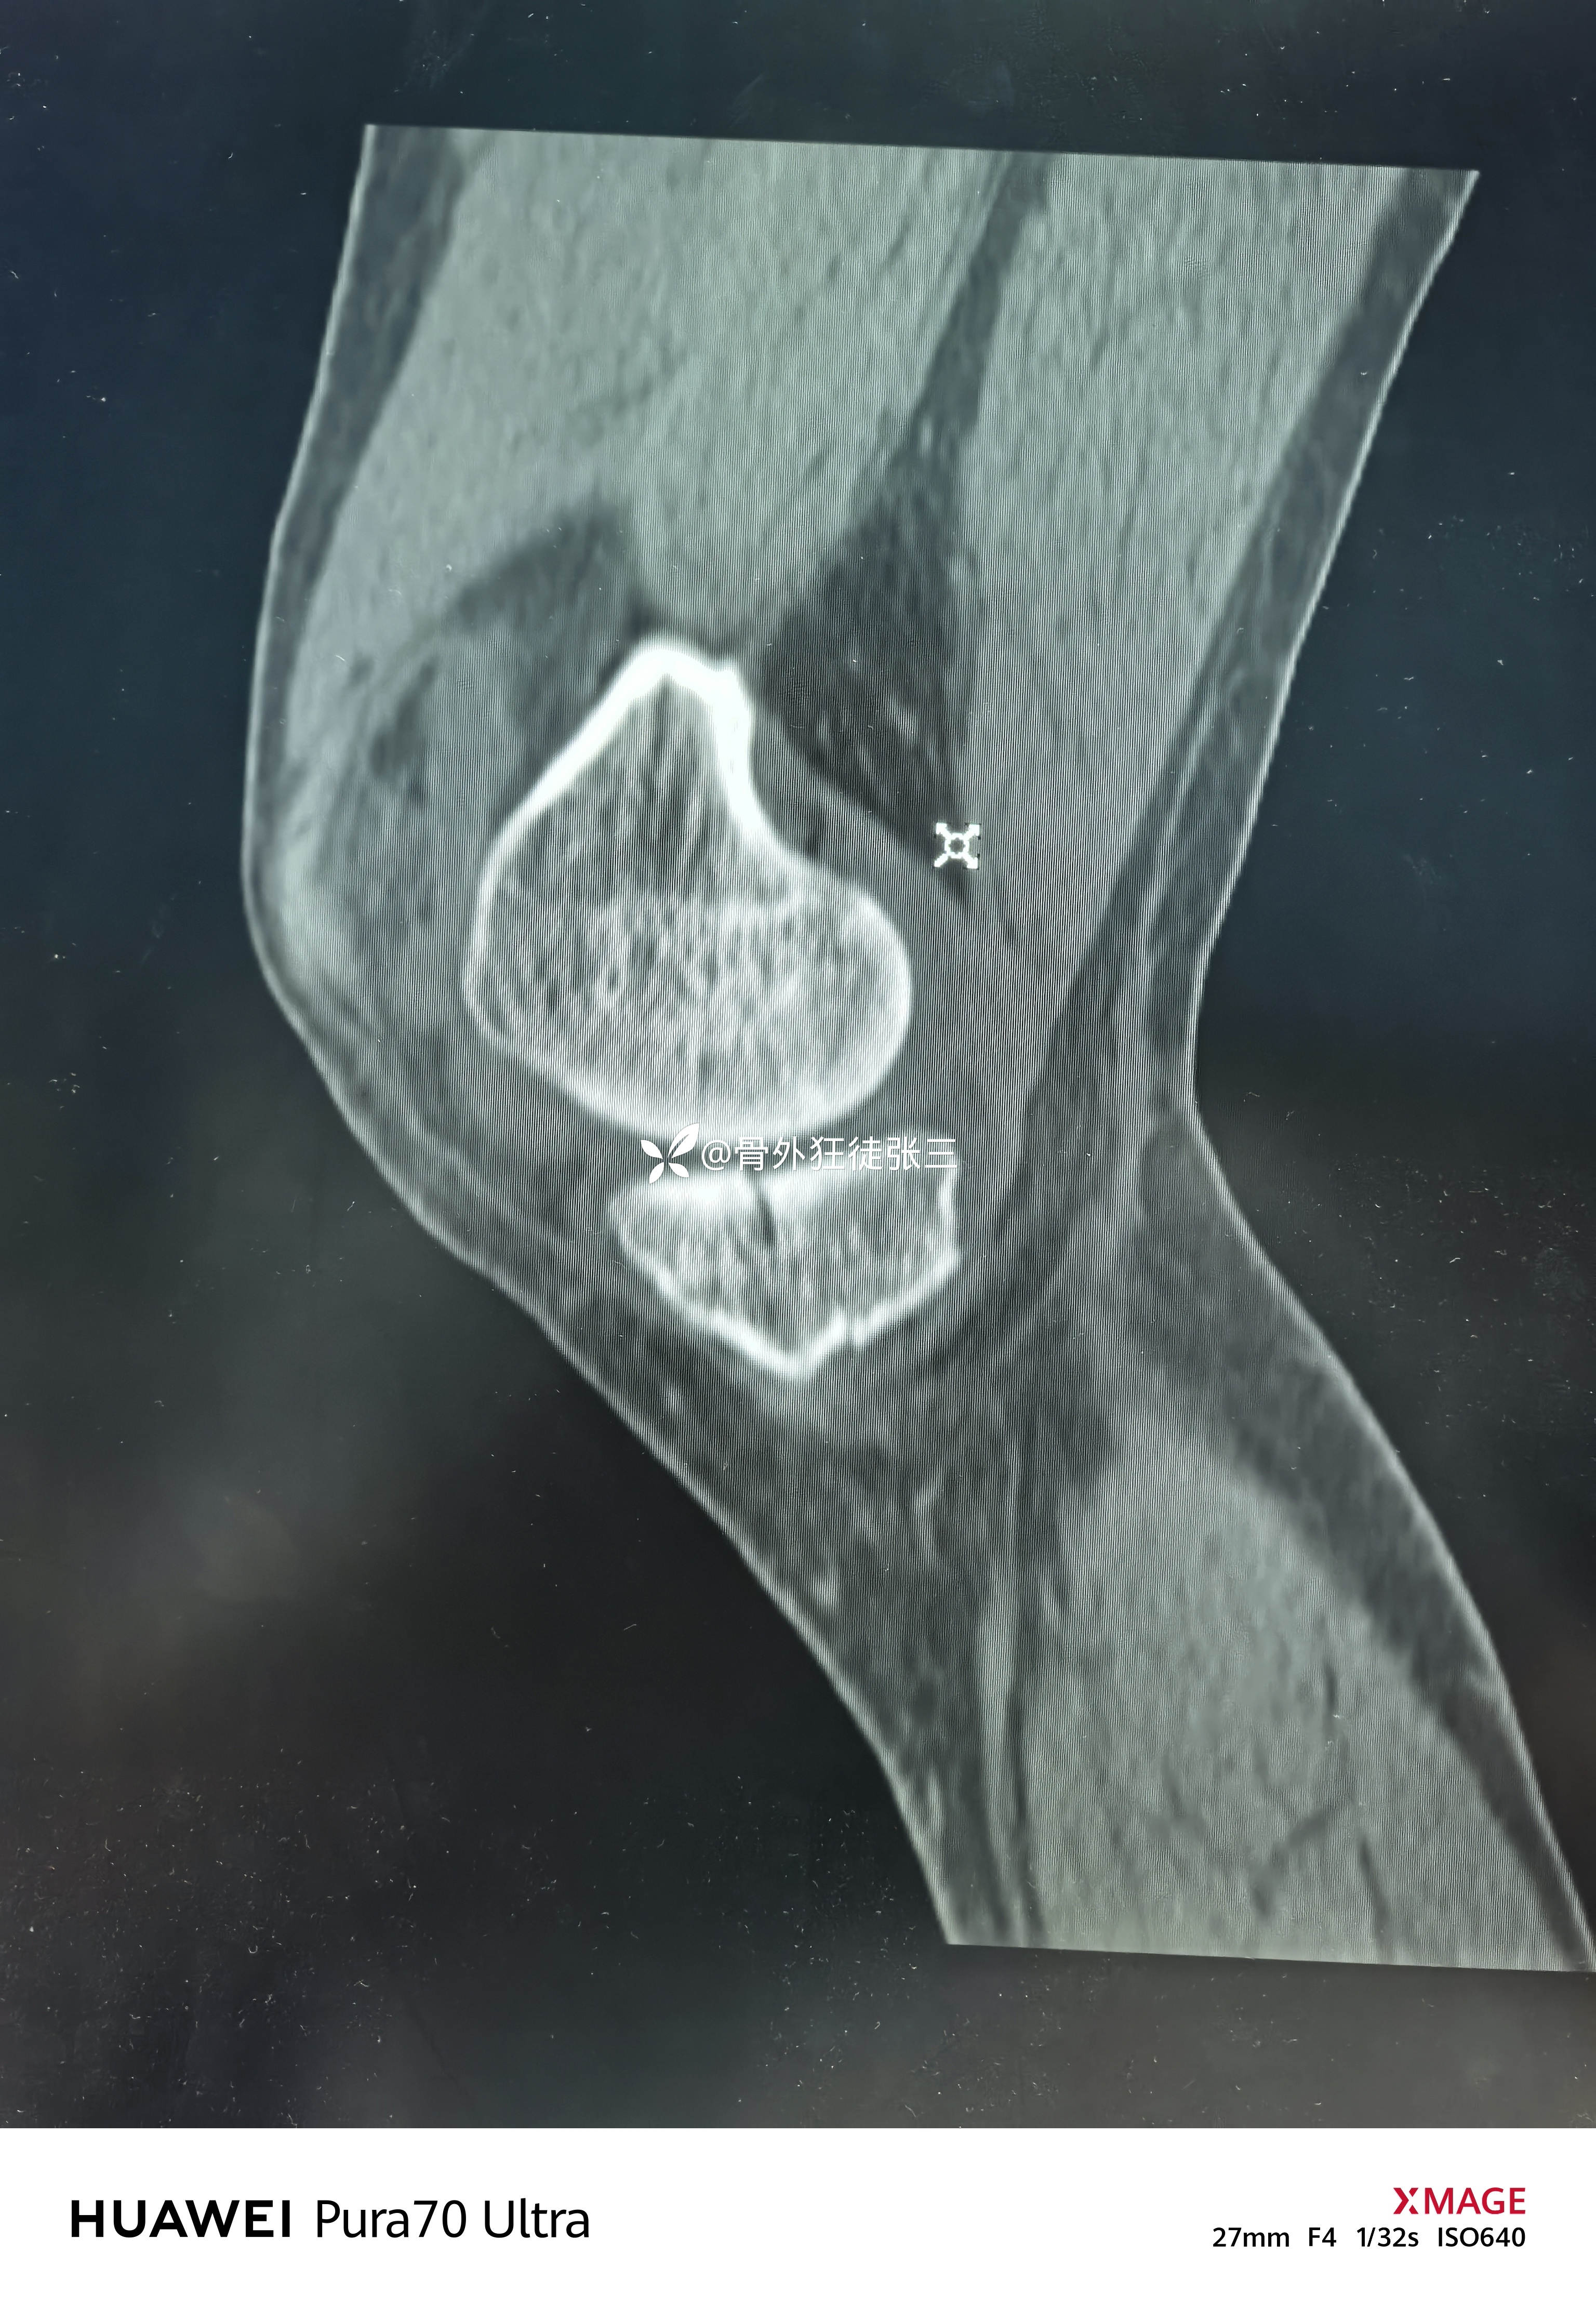

但是CT下显形惊涛骇浪

右胫骨平台骨折

(屈曲内翻型——后内侧平台骨折+外侧平台塌陷+ACL止点撕脱)